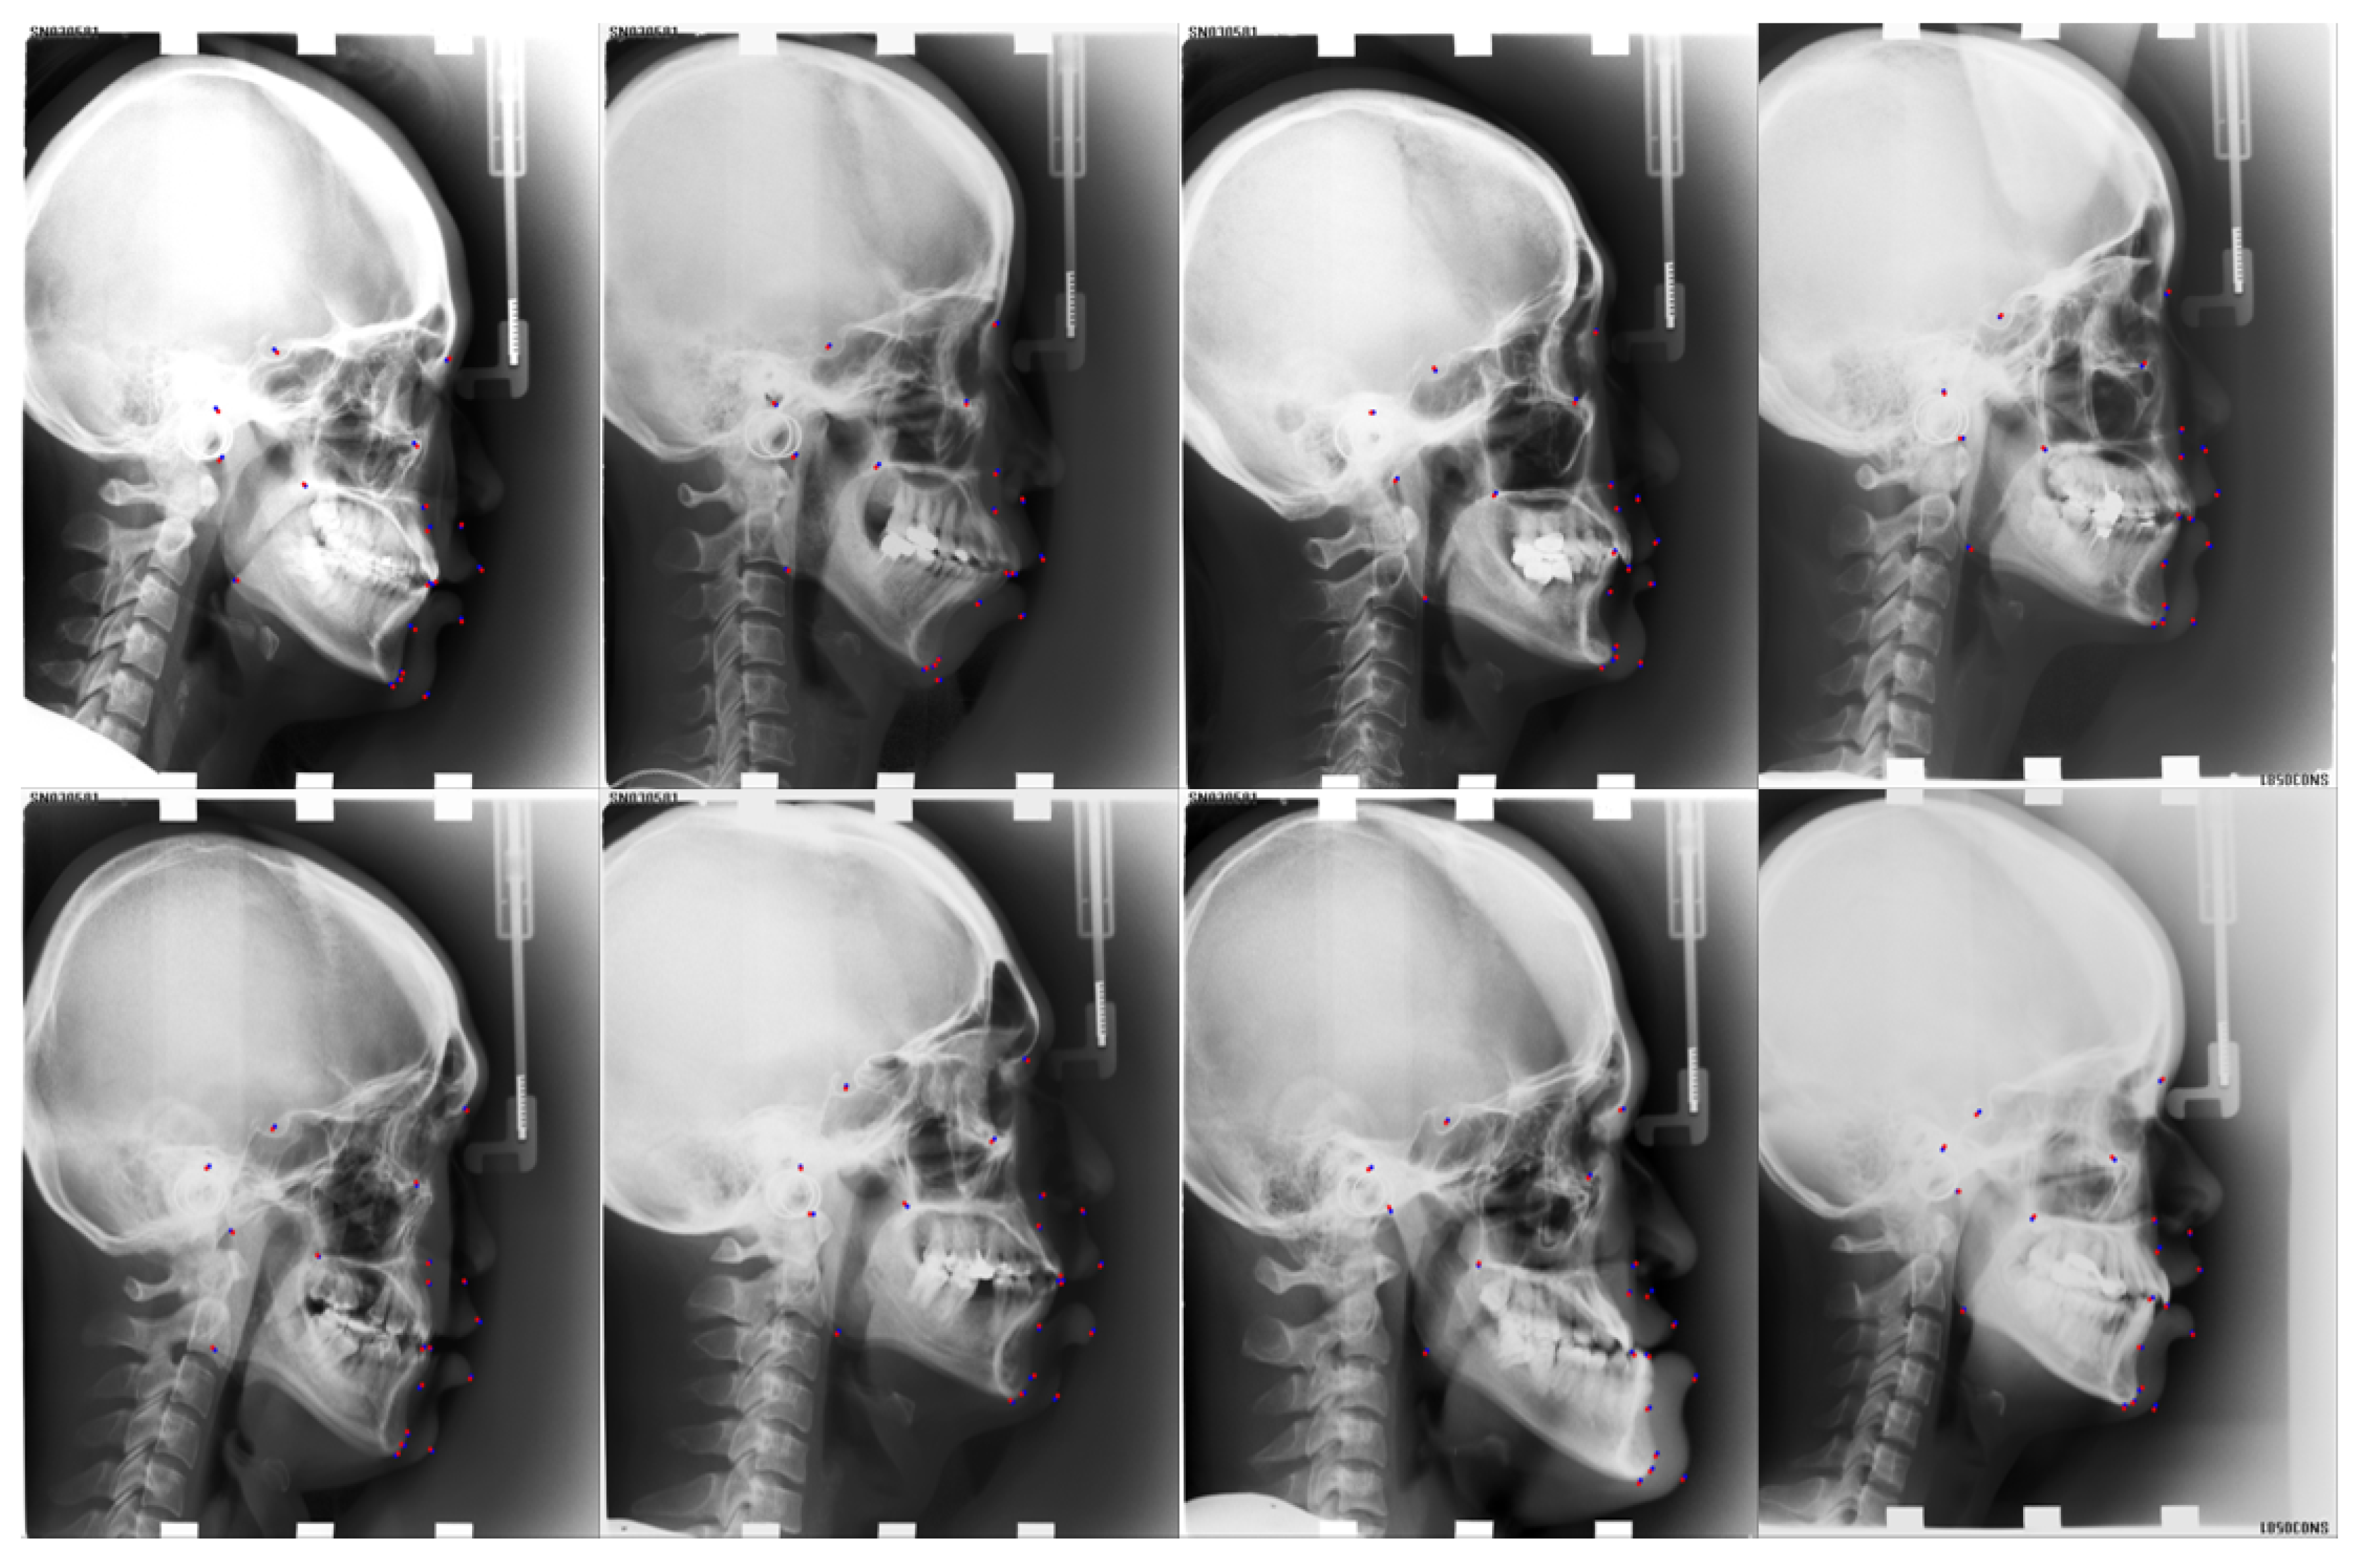

| Anatomical Name | Sella | Nasion | Orbitale | Porion | Subspinale | Supramentale | Pogonion | Menton | Gnathion | Gonion |

| Number | L11 | L12 | L13 | L14 | L15 | L16 | L17 | L18 | L19 | |

| Anatomical Name | Lower incisal incision | Upper incisal incision | Upper lip | Lower lip | Subnasale | Soft tissue pogonion | Posterior nasal spine | Anterior nasal spine | Articulate |